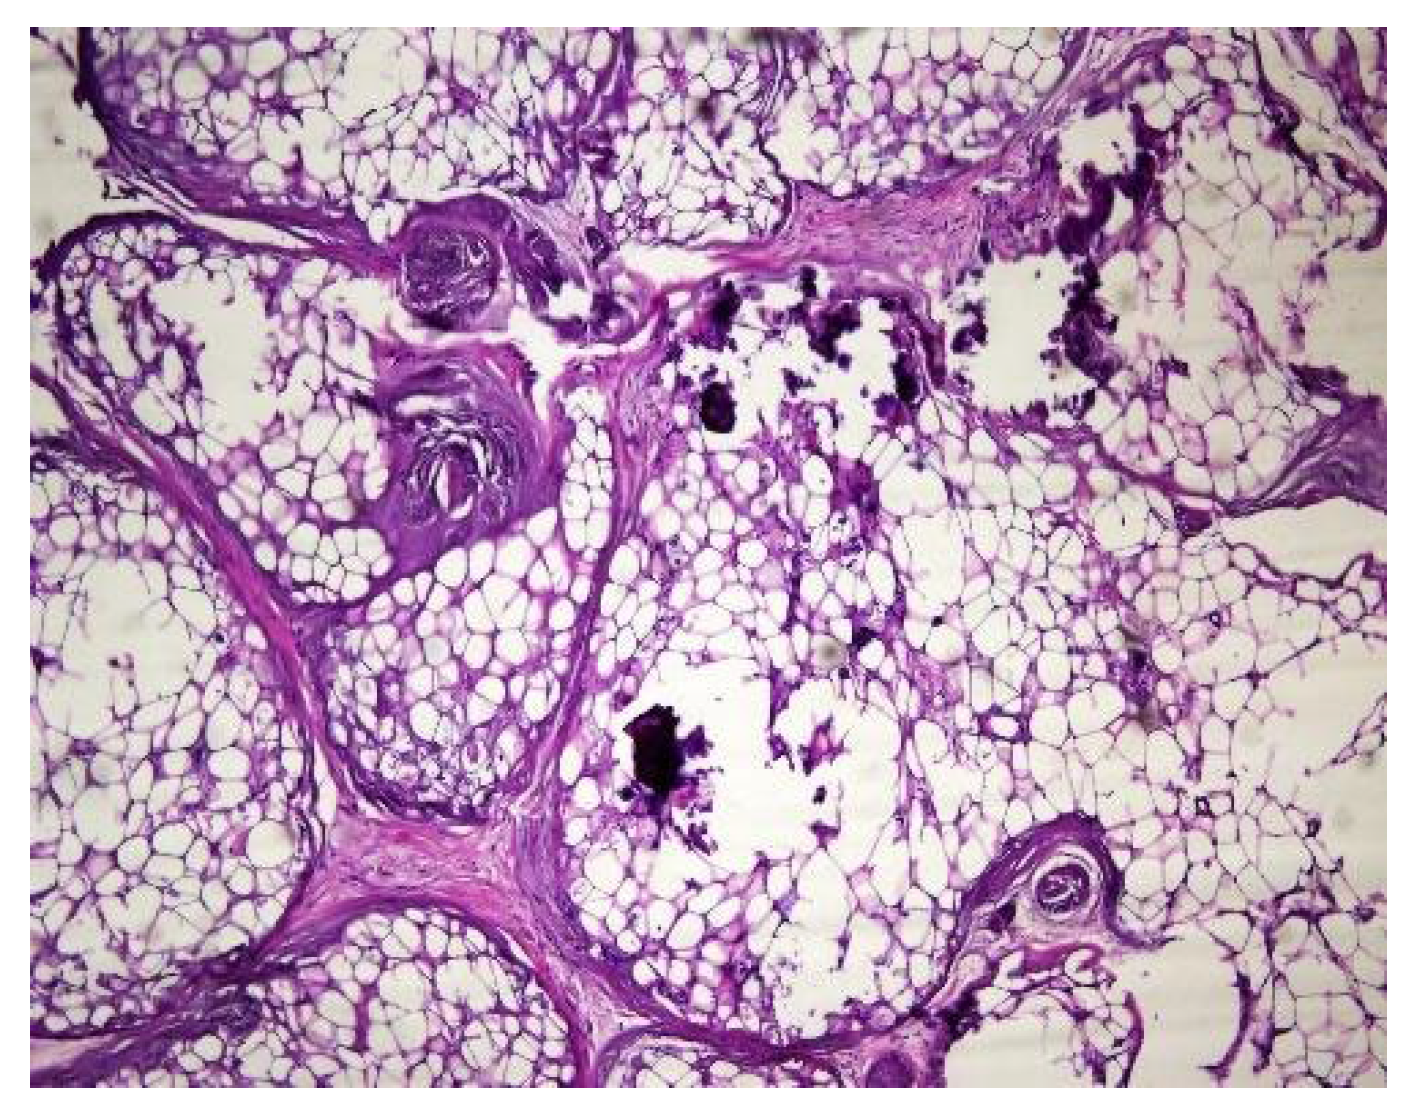

In both of the described cases, optical microscopy revealed lamellar fibrosis, deposits of fibrin on the surface of the peritoneum (Figure 3 and Figure 4) and dystrophic calcifications in the peritoneum (Figure 5 and Figure 6).

Several studies have attempted to identify and/or standardize the morpho-pathological changes in EPS, differentiating it from PS, which is a common occurrence in patients receiving PD and presents as a simple sclerosis [12,13,22,34,35]. The most frequent aspects observed were fibrin deposits, fibroblast swelling and mononuclear cell infiltration [11,12,22]. Garosi et al. investigated 39 biopsies from patients with EPS and found that tissue and arterial calcification, the thickening of the submesothelial layer and vasculopathy were the most significant observed changes [30]. In another study, Sherif et al. found that only fibrin deposits and the thickening of the compacta were significant [36]. In the present study, lamellar fibrosis, decreased cellularity, low grade perivascular inflammation and dystrophic peritoneal calcifications were frequent histological changes. Similarly, Braun et al. attempted to standardize the lesions and to define reproducible histological parameters in patients with EPS. It was found that calcification was a highly indicative criteria for EPS. Furthermore, mesothelial denudation, chronic inflammation, fibrin deposits, decreased cellularity and the presence of fibroblast-like cells were also indicative of EPS [10].

Figure 3. Lamellar fibrosis, condensed fibrin on the surface of the peritoneum and decreased cellularity (hematoxylin and eosin staining, original magnification × 100).